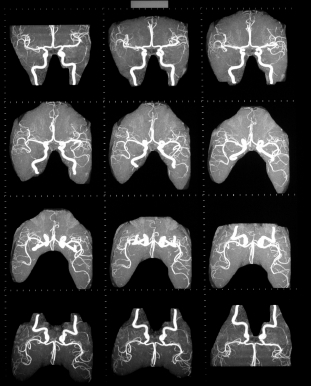

При подозрении на инсульт, пациент должен быть срочно госпитализирован и обследован. В диагностике обычно используется компьютерная томография, магнитно-резонансная томография. При отсутствии возможности проведения этих методов, диагностика менее достоверна и является результатом анализа клинической картины, данных спинномозговой пункции (в ликворе присутствует кровь), эхоэнцефалоскопии, дуплексного сканирования и церебральной ангиографии. Также необходимо исследовать: электролиты сыворотки крови, показатели функции почек, ЭКГ, маркеры ишемии миокарда, клинический анализ крови, протромбиновый индекс, насыщение крови кислородом.

Медицинские процедуры, проводимые при заболевании инсульт: Спиральная компьютерная томография, Магнитно-резонансная томография, Биохимический анализ крови, Клинический анализ крови, ЭКГ, Рентген, Спинальная пункция, Эхоэнцефалография, Дуплексное сканирование брахиоцефальных артерий (БЦА), Ангиография, Протромбиновое время, Протромбиновый индекс, Исследование газов крови